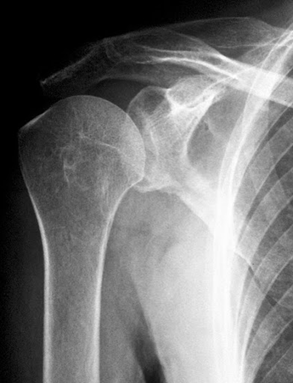

РОЗПІЗНАЙТЕ НА РЕНТГЕНОГРАМІ СУГЛОБ, ЩО МАЄ МІЛКУ СУГЛОБОВУ ЗАПАДИНУ І СКРІПЛЕНИЙ ПЕРЕВАЖНО М'ЯЗАМИ, ТОМУ ТУТ ВІДНОСНО ЧАСТО БУВАЮТЬ ВИВИХИ.

варіанти відповідей

НА ЯКИЙ СУГЛОБ ВКАЗУЄ СТРІЛКА НА РЕНТГЕНОГРАМІ? КІСТКИ ЯКОГО ВІДДІЛУ СКЕЛЕТУ ВІН З'ЄДНУЄ?

ГРУДНИННО-КЛЮЧИЧНИЙ С.

ПЛЕЧОВИЙ С.

НАДПЛЕЧОВО-КЛЮЧИЧНИЙ С.

АКРОМІАЛЬНО-КЛЮЧИЧНИЙ С.

КІСТКИ ВЕРХНЬОЇ КІНЦІВКИ

КІСТКИ ТУЛУБА І ВЕРХНЬОЇ КІНЦІВКИ

РОЗПІЗНАЙТЕ НАЙРУХОМІШИЙ СУГЛОБ ТІЛА ЛЮДИНИ, А ТАКОЖ СУГЛОБИ І КІСТКИ З ПЕВНИМИ ДІАГНОЗАМИ.

ДЕ ВИ БАЧИТЕ СУГЛОБ, ЯКИЙ ЗАБЕЗПЕЧУЄ РУХИ ПЛЕЧА.

ДЕ ВИ БАЧИТЕ СУГЛОБ, ЩО ЗАБЕЗПЕЧУЄ РУХИ ПЛЕЧА?